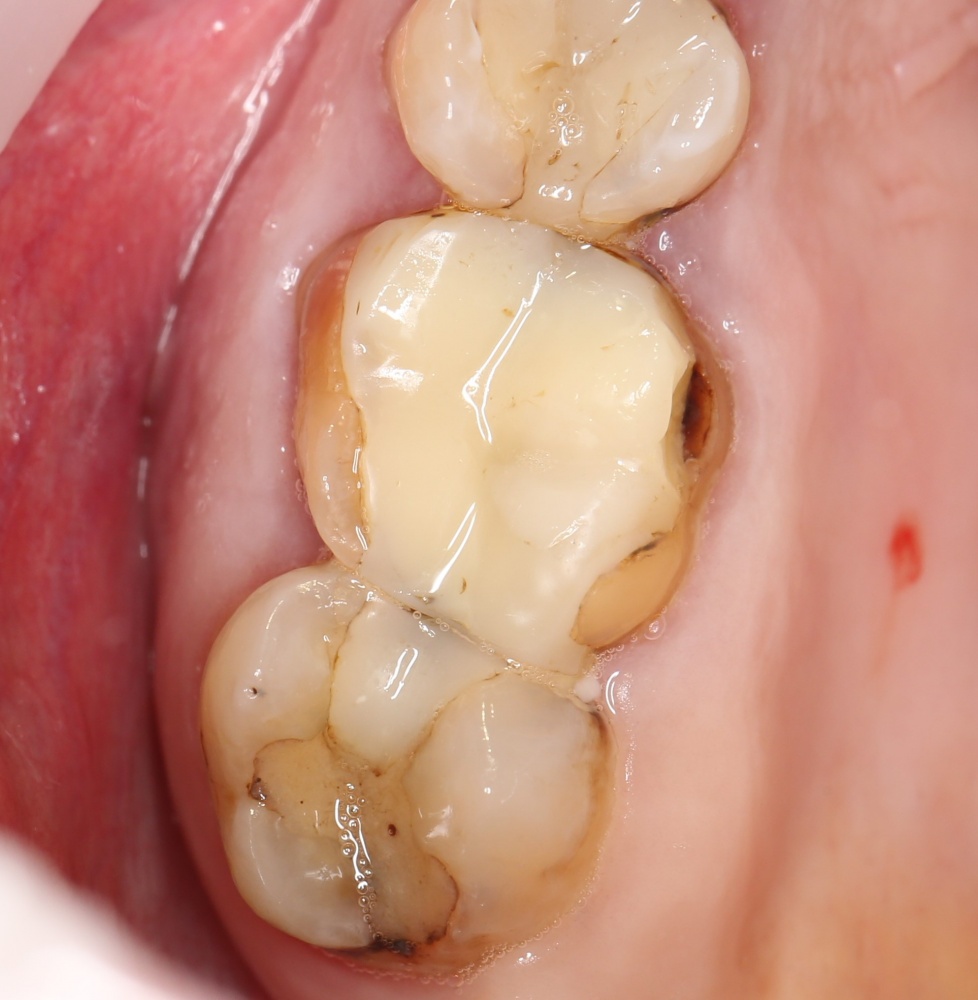

Через неделю я снял швы, а мой коллега Андрей Карнеев (дело было еще в НИЦ) приступил к изготовлению протезов. На это ушло полторы недели:

«Ого, какие классные зубы!» — сказала тогда Зинаида, после чего мы попрощались и договорились встретиться через полгода-год для замены временного протеза на постоянный керамический. Зинаида вернулась домой, в дружественную среднеазиатскую страну.

Но… в начале 2025 года я получаю от Зинаиды письмо, в котором она просит закончить лечение. Я с ужасом ожидал каких-нибудь жалоб и проблем (всё же, 11 лет без наблюдения стоматолога), но оказалось, что Зинаида просит поменять износившиеся временные коронки на постоянные. Да-да, ты не ослышался! Она 11 лет пользовалась временными коронками, и всё, что её беспокоит — это износ временных коронок!. Это абсолютный рекорд, я считаю.

Мы встретились как старые друзья. Честно признаюсь, я очень переживал. Я ожидал увидеть какую-нибудь жуть, утраченную кость, периимплантит, разрушенный вхлам протез и всё такое. Но… всё оказалось не так плохо: